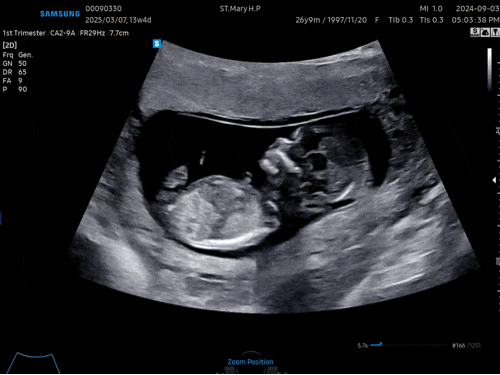

임신 13주 14주차 기록 (아들일까? 딸일까?)

13주 3일 처음 씩씩이의 존재를 알게된 날 6월 22일, 미국에 가기 전 몸무게를 쟀을 때는 분명 49kg였는데?...

씩씩이가 찾아와준 순간, 임밍아웃

24년 8월 어느날, 나지 않던 트러블이 이마에 너무 많이 나고, 생리도 안 하고, 기분도 왔다 갔다 하고, 식...